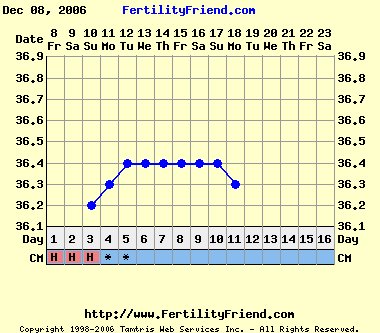

Addig is a semleges görbém.